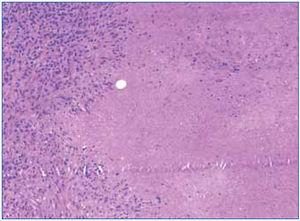

Se realizó biopsia de una adenopatía cervical, en la que se objetivó inflamación granulomatosa epitelioide con extensa necrosis caseosa (figura 1). En la tinción de Ziehl-Nielsen se observaban escasos bacilos (figura 2).

Figura 1. Extensos focos de necrosis caseosa en la biopsia del ganglio supraclavicular derecho.